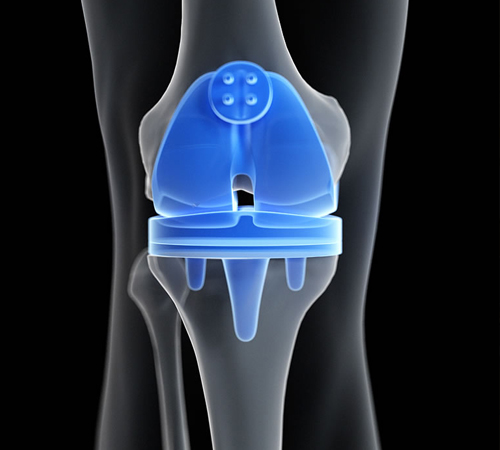

Primary & Revision Joint Replacement,

Primary & Revision Joint Replacement,